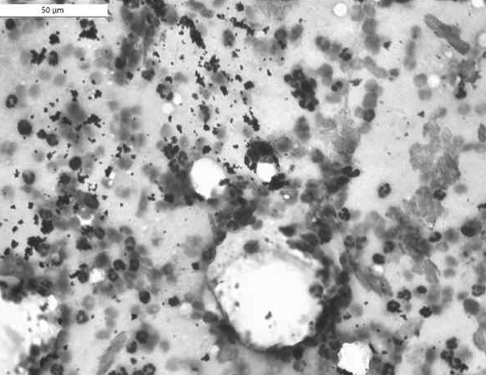

- Thick fluid with some neutrophils : basophilicํ๊ฒ ์ผ์๋ mucus + ๊ณตํฌ๋ค (ํ์ก์ ์ฃผ๋ณ์ ๊ฑฐํ์ด ์๊ฒ ์์ผ๋ฏ๋ก) + segmented neutrophil์ด๋ RBC๋ ๊ด์ฐฐ๋ ์ ์์

- foamyํ cytoplasm์ ๊ฐ์ง ์ธํฌ = active macrophage. (์ค๋ฅธ์ชฝ ์ฌ์ง)